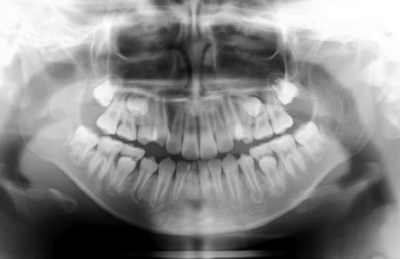

9歳の男児。上顎両側犬歯の位置異常を主訴として来院した。前歯部で早期接触が認められたが、下顎位の前方偏位は0.5mm程度であった。初診時の顔面写真、口腔内写真及びエックス線写真を示す。セファロ分析の結果を図に示す。

第一期治療における治療方針で適切なのはどれか。2つ選べ。